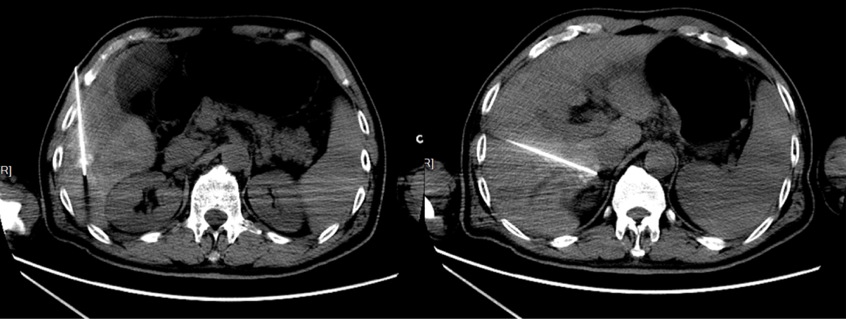

2015-07-16,联合RFA。

2017-10-23,第2次RFA。

治疗方案:第3次RFA联合索拉非尼